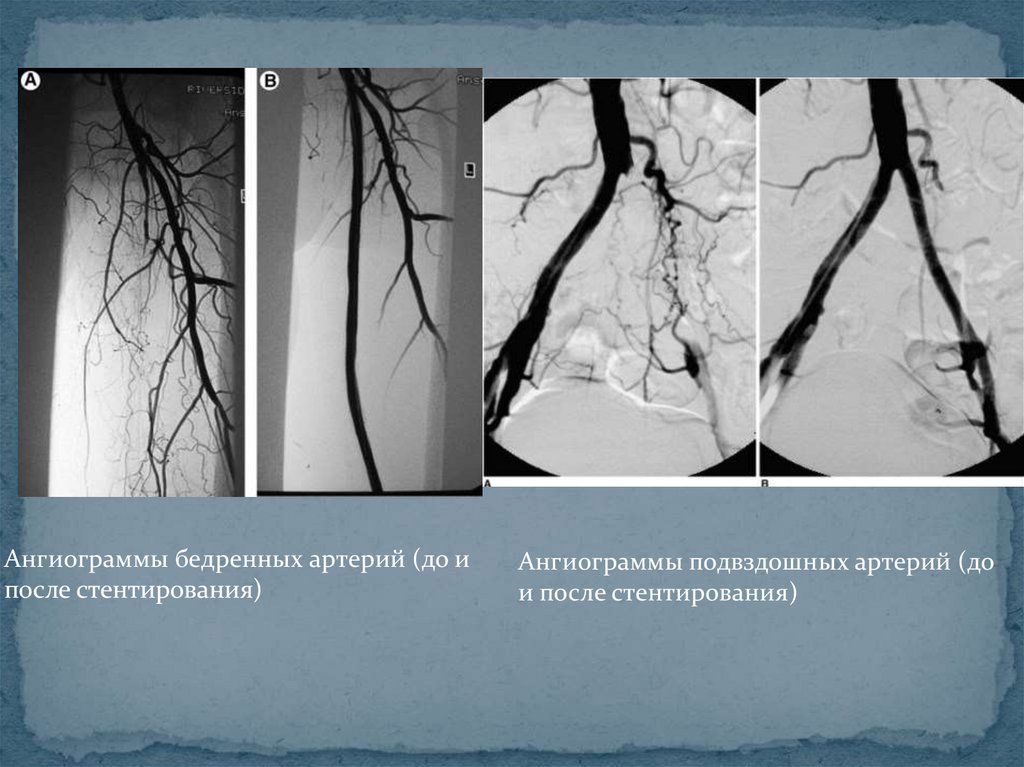

Ангиограммы бедренных артерий (до и

после стентирования)

Ангиограммы подвздошных артерий (до

и после стентирования)